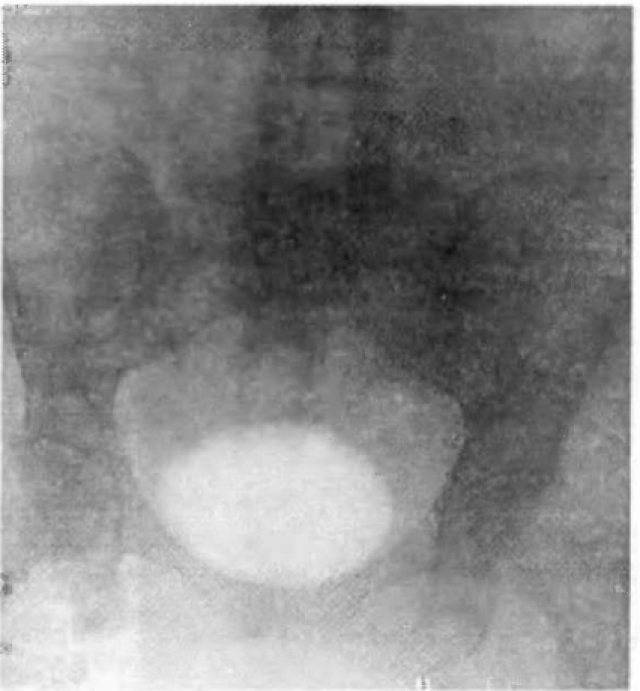

Медицинские изображения и примеры эксреторной цистографии